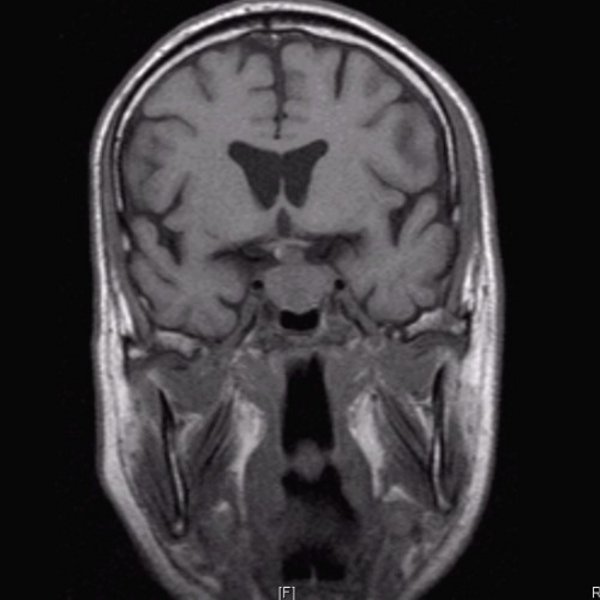

Hypophysenadenom T1 cor